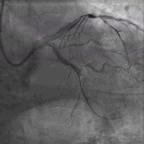

冠状动脉造影结果显示冠状动脉三支血管严重病变,左主干内膜不光滑但无狭窄,前降支开口狭窄95%,近段狭窄80%,D1内膜不光滑且近段狭窄80%,回旋支远段狭窄99%,OM1开口狭窄90%,OM2闭塞,右冠状动脉近段狭窄60%~80%,中段闭塞(图2)。SYNTAX评分46分。

图2. 冠状动脉造影